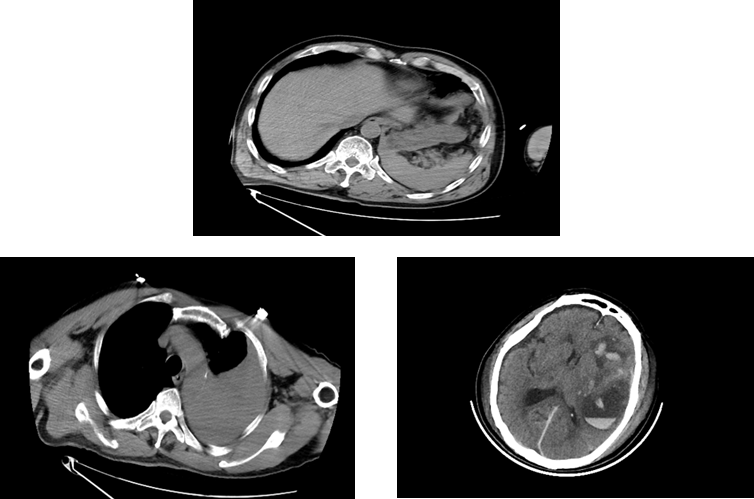

120急救车将居先生(化名)送至我院抢救室时,情况已经万分危急,时间就是生命!急诊抢救室团队立即启动应急预案,心电监护、吸氧、建立静脉通道、床边超声FAST筛查等抢救措施一气呵成。全身CT扫描提示患者全身上下存在颅脑、胸腔、腹腔等多处致命损伤。